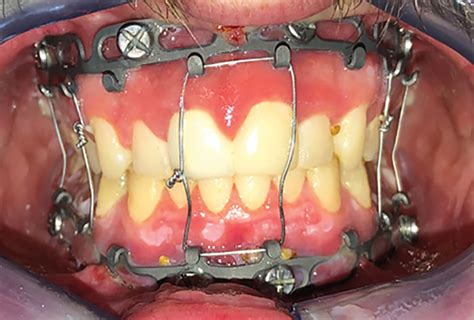

Maxillomandibular Fixation | Jefferson Health